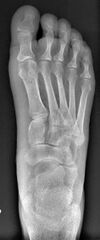

Bunion (hallux valgus) deformity is actually part of a complex of anatomical derangements of protruding mass (bunion), buckling of big toe (hallux valgus) and the bone behind it (metatarsus primus varus), displaced sesamoid bones (detrimental to the important walking function of big toe), collapsed metatarsal arch and several other secondary changes that are the domino effects of metatarsal primus varus. Thus, metatarsus primus varus correction has become the primary objective of all bunion surgeries.[citation needed]

Primus varus deformity is the leaning of the first metatarsal bone away from the second metatarsal and towards the opposite foot (Fig. 1). As it leans over, its head sticks out to form the bunion bump and it also widens the forefoot to cause shoes feeling too tight. Thus when bunion pain becomes unmanageable, surgical correction is to narrow the forefoot by repositioning of the first metatarsal head back to its normal position. This can be done by osteotomy (bone-breaking), soft tissue (non-osteotomy) or fusion techniques.[citation needed]

Syndesmosis procedure addresses specifically the two fundamental problems of metatarsus primus varus deformity that gives rise to the bunion deformity. They are leaning and instability of the first metatarsal bone . Syndesmosis procedure uprights the leaning first metatarsal bone with strong binding sutures between it and the second metatarsal bone (Fig. 2) and then also stabilizes it uniquely by creating a fibrous connecting bridge between these two bones (Fig. 3, 4). First metatarsal bone can be readily realigned because by definition of the metatarsus primus varus deformity its first metatarsal is abnormally loose and mobile.[citation needed]